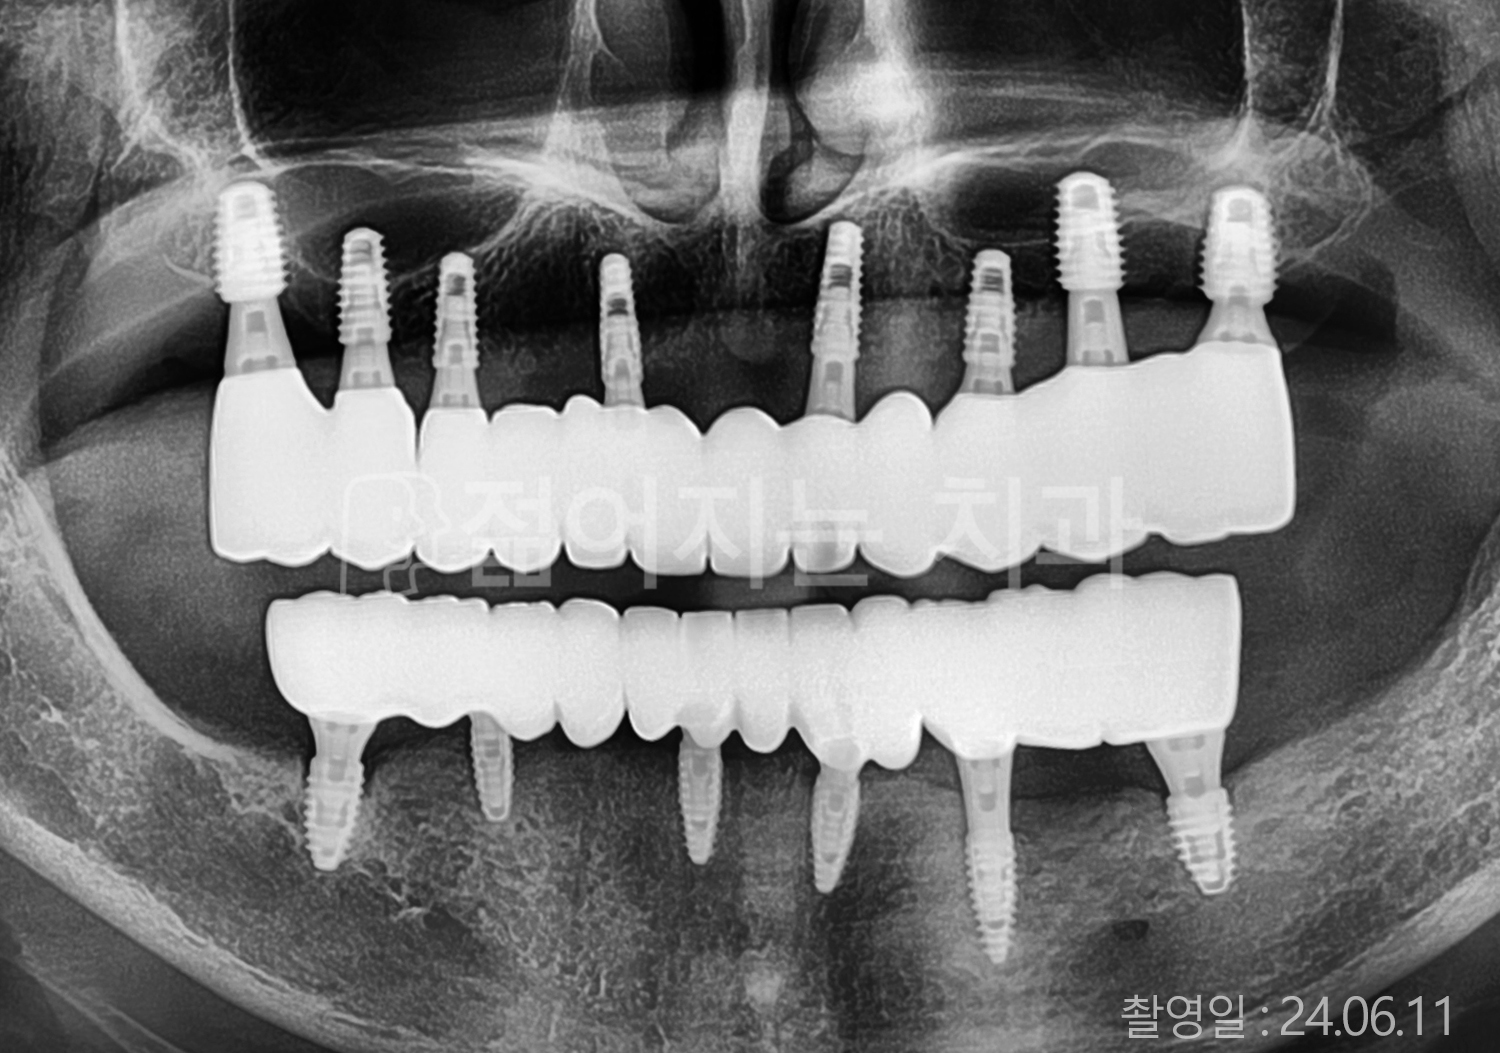

• 70대 고혈압, 당뇨 전체치아 10개 이상 임플란트

• 50대 고혈압, 당뇨 전체치아 10개 이상 임플란트

• 60대 고혈압, 당뇨 전체치아 10개 이상 임플란트

• 50대 전체치아 10개 이상 임플란트

• 70대 당뇨 전체치아 10개 이상 임플란트

• 80대 전체치아 10개 이상 임플란트

• 40대 전체치아 10개 이상 임플란트

• 60대 고협압, 고지혈증 전체치아 10개 이상 임플란트

• 60대 전체치아 10개 이상 임플란트